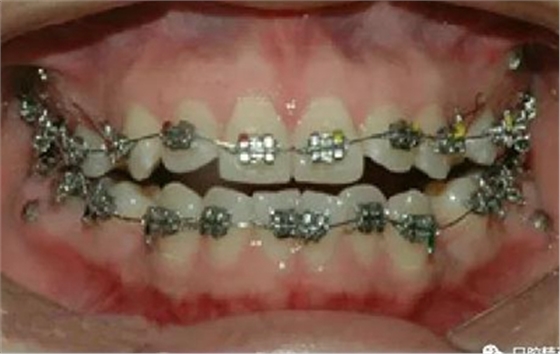

微型種植釘直徑僅有1.6mm和2mm,植入部位幾乎可以不受限制,可植入牙槽骨的任何部位,微型種植體支抗植入手術(shù)操作簡單、安全,不需要牙齦翻瓣,即可旋入微型種植體,整個(gè)手術(shù)過程僅需5-10min,術(shù)后患者的不良反應(yīng)少,微型種植體的取出亦非常簡單,甚至不需局部麻醉,將其反向旋出即可。自攻型種植釘植入牙槽骨中起支抗作用.

一般情況下是成年人使用,特殊病例十三、四歲的小孩可以用。種植釘可以打在牙槽骨的任何部位。可以在2個(gè)牙齒之間的牙槽骨上打釘,或者打在頰側(cè)牙槽骨與牙根之間,主要看你是如何應(yīng)用支抗了。2個(gè)牙齒之間的牙槽骨上打釘,支抗作用拉動的牙齒有限,而打在頰側(cè)牙槽骨與牙根之間可以將整個(gè)牙列拉向遠(yuǎn)中移動。種植支抗釘在矯正結(jié)束后要拿下來。